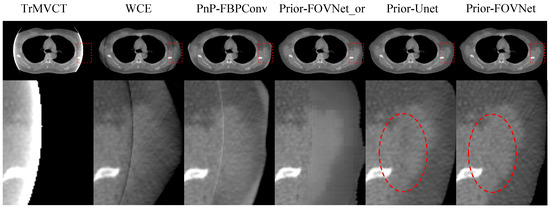

4.3. Results of Clinical Patient Data